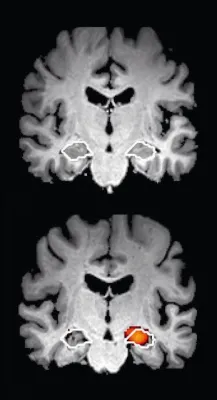

Die häufigste Form der Demenzerkrankungen ist die Alzheimer-Demenz ("Alzheimer"). Rund 60 Prozent aller Demenzen werden durch eine Alzheimer-Demenz hervorgerufen. Bei dieser Krankheit gehen in bestimmten Bereichen des Gehirns durch Störungen des Gleichgewichts des Botenstoffs Glutamat Nervenzellen zugrunde. Man spricht auch von einer neurodegenerativen Demenz.